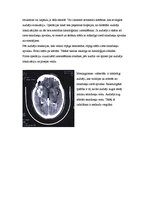

Vienas no akūtām operācijām ir galvas traumas, kur laikam ir zināma nozīme pēcoperācijas perioda iznākumā. Tādēļ operācijas sagatavošanas posmam jābūt pēc iespējas īsākam.

Traumas rezultātā iespējams izveidoties 4 pamatbojājumu veidiem:

1. Epidurāla hematoma

2. Subdurāla hematoma

3. Intracerebrāla hematoma

4. Galvaskausa impresijas lūzumi